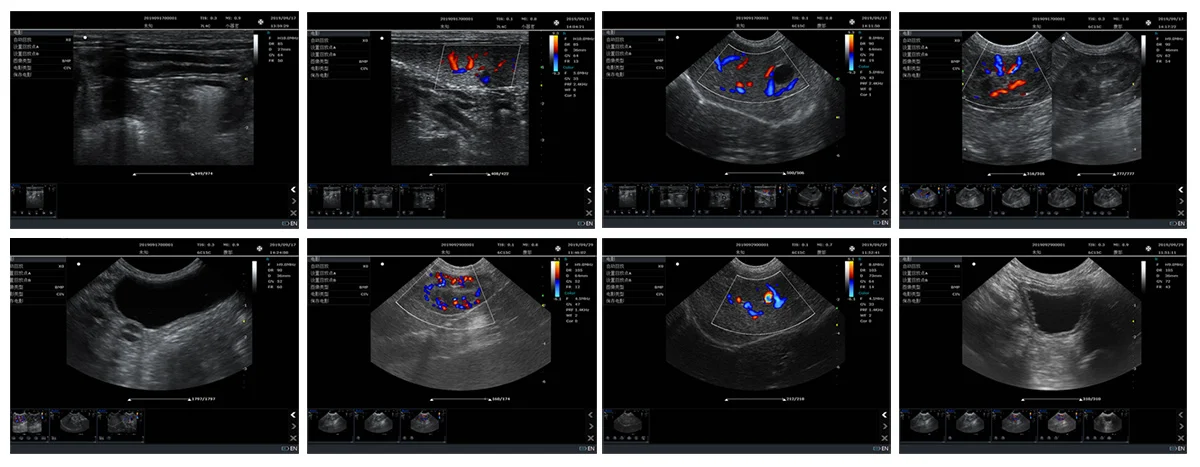

Full Digital Mobile Echocardiography Cardiac Echo Ultrasound Scan Color Doppler Ultrasound Machine for Pregnancy

Color Doppler ultrasound diagnosis system

Abdomen, gynecology, obstetrics, pediatrics, Urology, transvaginal, superficial, blood

vessels, small organs, abdomen, pediatrics.